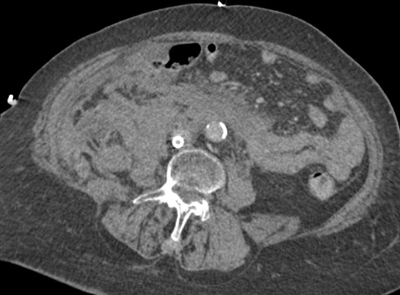

Figure 1

An axial CT of extensive intra- and retroperitoneal blood at the level of the infrarenal aorta.